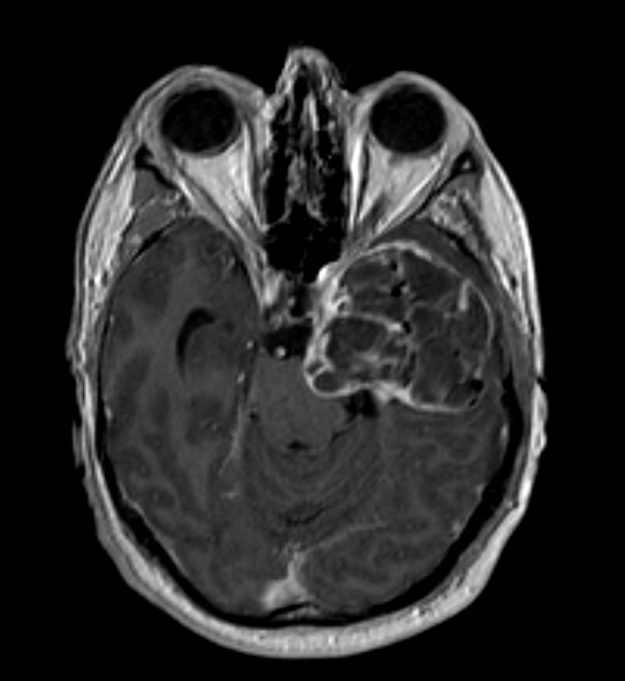

Μηνιγγίωμα περιοχής Επίφυσης

Ασθενής γυναίκα, 52 ετών η οποία παρουσίασε υπακουσία και επεισόδια πάρεσης του προσώπου. Ο απεικονιστικός έλεγχος με μαγνητική τομογραφία ανέδειξε ευμεγέθη όγκο στην περιοχή της επίφυσης (κωνάριο) με πίεση επί του μεσολοβίου, του τετραδύμου πετάλου και λοιπών εν’ τω βάθει δομών. Διενεργήθη δεξιά ινιακή, διασκηνιδιακή, διαδρεπανική προσπέλαση και ολική αφαίρεση της βλάβης. Η μετεγχειρητική αξονική…